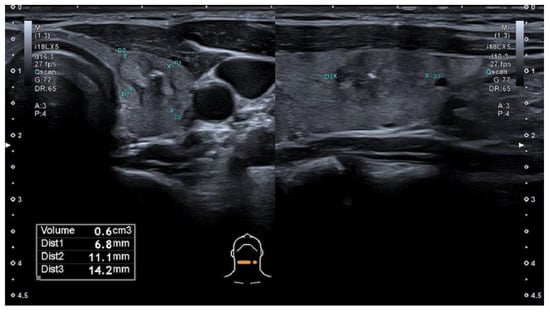

The modified Kwak et al. TIRADS system [21] that is used in Latvia (L-TIRADS) is based on the count of suspicious signs of ultrasound, which include marked hypoechogenicity, microcalcifications, taller than wide shape, irregular or microlobulated/ spiculated margins and metastatic lymph nodes. TIRADS 1—normal thyroid tissue without nodules. TIRADS 2 includes simple cysts, spongiform nodules, hyperechogenic nodules in patients with chronic autoimmune thyroiditis; multinodular hyperplastic goiter without separate bounded nodules; isolated macrocalcifications. TIRADS 3 includes partly cystic nodules; solid nodules with isoechogenic, hyperechogenic, moderately hypoechogenic structure, without any independent sign of malignancy (Figure 1 and Figure 2). TIRADS 4A—one ultrasonographic sign of malignancy, 4B—two ultrasonographic signs of malignancy, 4C—three ultrasonographic signs of malignancy, and 5—four and more ultrasonographic signs of malignancy.

Figure 2. Hypoechogenic nodule, ovoid shape, smooth margins, non-homogeneous solid thyroid nodule with cystic component and macrocalcification in its structure—TIRADS 3 by modified Kwak et al. (L-TIRADS), TIRADS 4 by European and Korean TIRADS, TIRADS 5 by ACR TIRADS systems. FNA biopsy results—Bethesda 2.